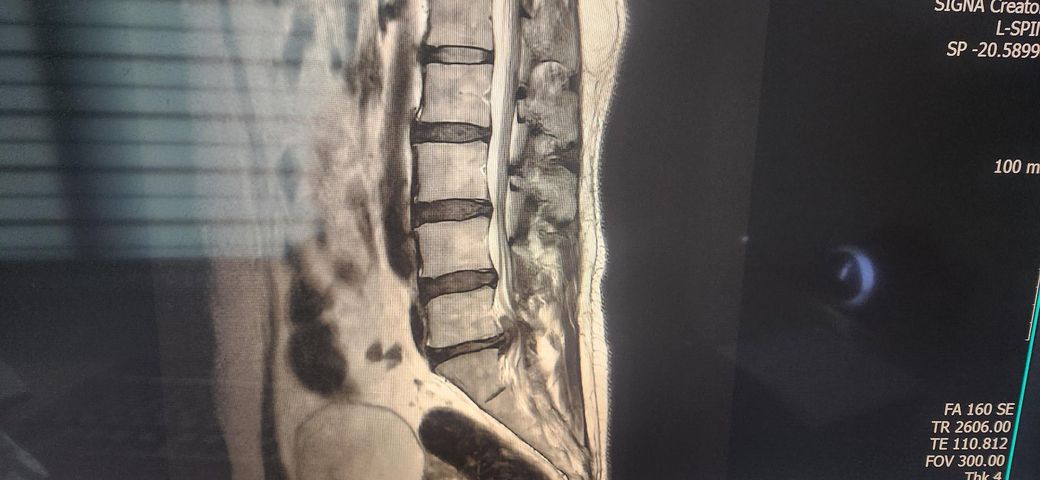

첫번째 사진이 12월 28일 수술 전 사진입니다.

5번과 1번 문제로 수술 받았습니다.

• 1번 째 사진